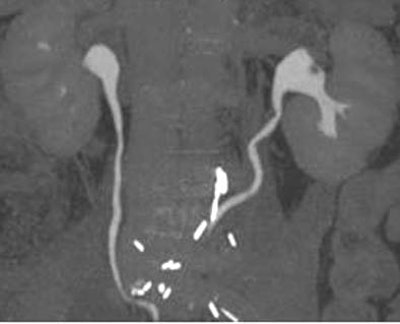

| Parenchymal phase (above), excretory phase (below), and MIP images (bottom) from a patient with a high-grade superficial recurrence of transitional cell carcinoma in the left renal pelvis. Images courtesy of Dr. Theresa Koppie. |

The researchers evaluated the CT images for hydronephrosis, filling defects, strictures, thickening, renal pelvis, ureters, anastomosis, and periureteral soft-tissue changes. They found 13 cases of hydronephrosis, nine patients with filling defects ranging from 5 mm to 1.5 cm, and seven patients with periureteral stranding. Periureteral stranding occurred most commonly in the distal left ureter in the region where it crossed the left mesentery, she said. Calculi were found in two patients. Eight of the 47 patients had cancer recurrence, all histologically proven transitional-cell carcinomas obtained during open surgery, Koppie said.

"All of the patients who developed some kind of a cancer in the upper tracts (renal pelvis, calyces, ureter) had a positive CT urogram," Koppie said. CT was 100% sensitive, and 30.8% specific, for upper-tract disease recurrence.

For the study, all of the patients underwent postsurgical follow-up CT surveillance using either a LightSpeed or LightSpeed Ultra CT scanner (GE Healthcare, Waukesha, WI) at 5-mm collimation, and following the peripheral IV administration of 140 cc of iodinated contrast, Koppie said. Unenhanced, parenchymal, and excretory-phase images were acquired. Follow-up imaging occurred from six months to three years post-surgery. The mean delay was 26.8 months with a median of 11 months, and patients are now followed up yearly, Koppie said.